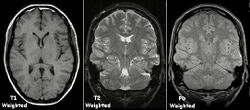

Examples of T1-weighted, T2-weighted and PD-weighted MRI scans

Each tissue returns to its equilibrium state after excitation by the independent relaxation processes of T1 (spin-lattice; that is, magnetization in the same direction as the static magnetic field) and T2 (spin-spin; transverse to the static magnetic field).

To create a T1-weighted image, magnetization is allowed to recover before measuring the MR signal by changing the repetition time (TR). This image weighting is useful for assessing the cerebral cortex, identifying fatty tissue, characterizing focal liver lesions, and in general, obtaining morphological information, as well as for post-contrast imaging.

To create a T2-weighted image, magnetization is allowed to decay before measuring the MR signal by changing the echo time (TE). This image weighting is useful for detecting edema and inflammation, revealing white matter lesions, and assessing zonal anatomy in the prostate and uterus.

| Proton density weighted |

PD |

Long TR (to reduce T1) and short TE (to minimize T2).[67]

|

Joint disease and injury.[68]

- High signal from meniscus tears.[69] (pictured)